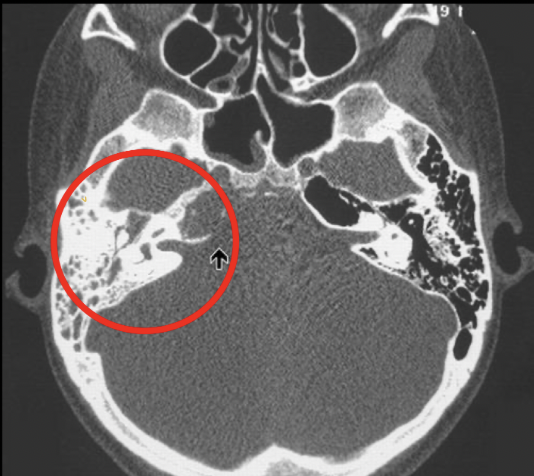

Q

Dx de la siguiente imagen

A

Matoiditis

Clave en imagneología para dx de mastoiditis

Opacificación de celdillas mastoideas+ colección de líquido (pus o moco)

Si es crónico vemos efecto esclerodiploico que es mastoides osificada